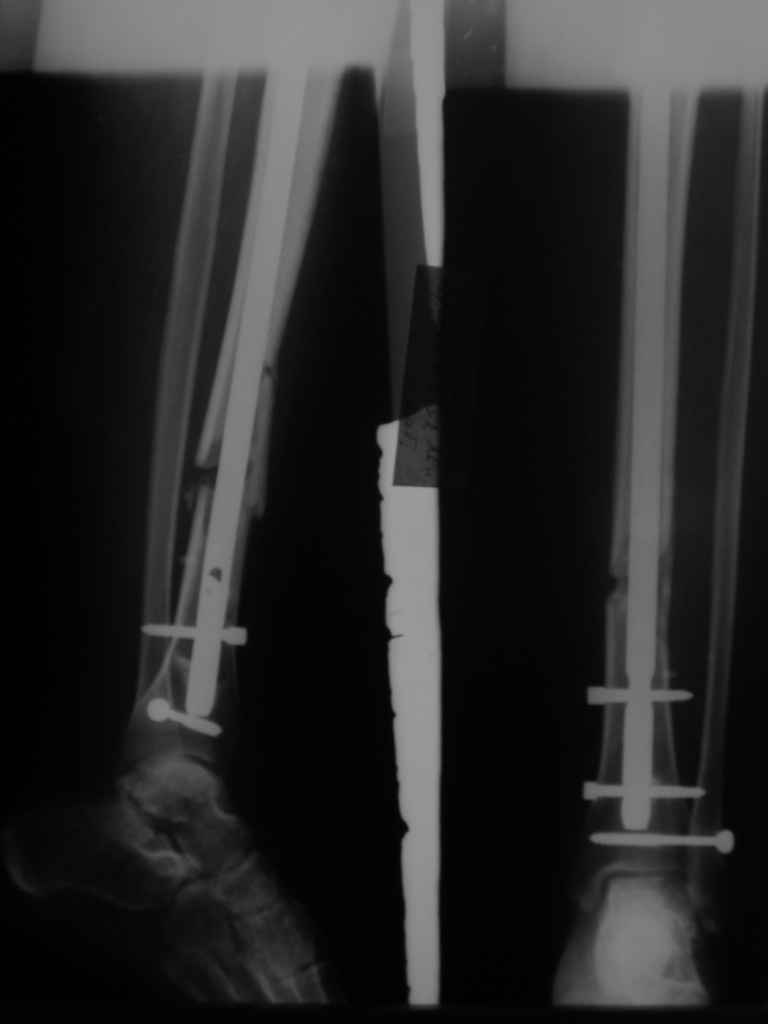

КА> Но почему решение динамизировать на сроке 8 недель с полным

В приложении картинка пациента со сломанным внизу гвоздем. Начал лечение в другом учреждении. Еще и адвокат к тому же.

Динамизировали через 8 недель, а оно поползло больше, чем хотелось бы.

В Кемпбелле можно прочитать, что Fractures in the distal third of the tibia had the highest frequency of nail breakage.

Вообще, этот вопрос обсуждался давно, и еще в статье R. Bucholz (1987) про переломы гвоздей указывалось, что расстояние от ближайшего отверстия до перелома должно быть не менее 5 см, иначе есть угроза усталостного перелома. По литературе переломы гвоздей в нижней трети

tibia достигают 4,3%.